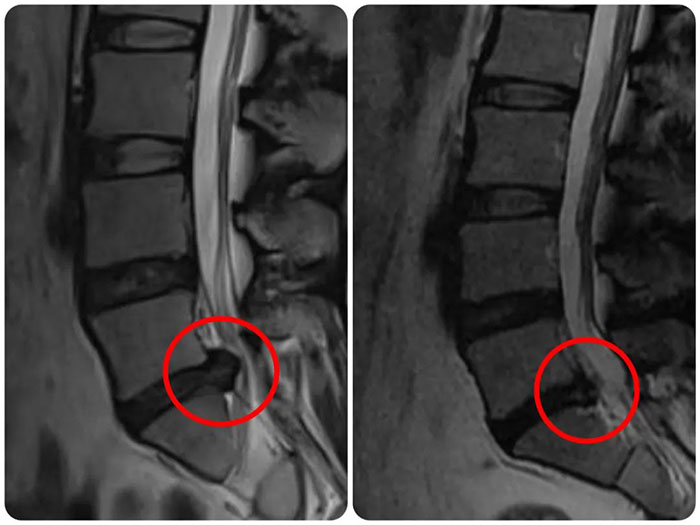

術(shù)前VS術(shù)后效果對(duì)比

入院后,經(jīng)過(guò)完善脊柱相關(guān)檢查,張先生被診斷為巨大型椎間盤突出癥(L5/S1節(jié)段)。趙曄主任團(tuán)隊(duì)根據(jù)患者情況分析病情,征求患者意愿后準(zhǔn)備為其制定UBE手術(shù)治療計(jì)劃。患者詳細(xì)了解了手術(shù)過(guò)程和康復(fù)事項(xiàng)后,欣然接受了這一治療方式。

手術(shù)在全麻下進(jìn)行,消除了患者局麻手術(shù)的恐懼及疼痛感,手術(shù)過(guò)程安全無(wú)痛,術(shù)前經(jīng)過(guò)嚴(yán)格準(zhǔn)備,透視確定責(zé)任節(jié)段及切口位置,采取兩個(gè)約1cm手術(shù)切口就順利完成了病變節(jié)段內(nèi)鏡下椎板開(kāi)窗+椎管減壓+髓核摘除術(shù),術(shù)后患者立即感覺(jué)下肢疼痛明顯緩解,術(shù)后第二天下地行走,癥狀明顯改善,患者對(duì)手術(shù)效果非常滿意。